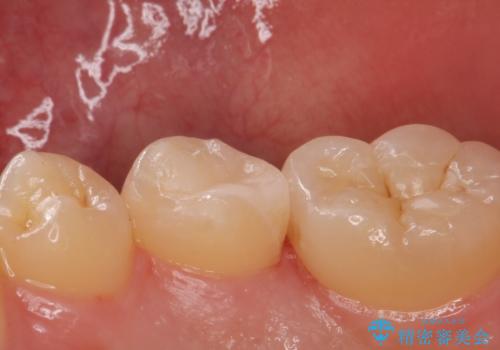

適合の良い詰め物が入りました。

歯と歯の間は歯ブラシだと磨くことができないので毎日歯間ブラシやフロスを使うことをお勧めします。